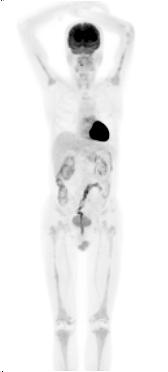

整体观察见MIP图(图3)。主要阳性发现包括:左心房、主动脉及肺动脉主干周围可见环形、弥漫性FDG摄取(SUVmax 3.8),但相应部位平扫CT未见明确异常结构改变(图4);右肾盂扩张,内见形态不规整FDG摄取增高软组织密度肿物影(SUVmax 4.9),边缘毛糙,范围约3.6 cm×2.9 cm×3.0 cm,并包绕上段输尿管,同时见右肾盂积水(图5);四肢长骨FDG摄取对称性增高(SUVmax 3.2),自关节端向骨干伸,相应部位CT见不规则骨质硬化,其中右股骨内侧髁可见溶骨性骨质破坏(图6);脊柱及骨盆亦可见多发性质类似的骨病变(图7、8)。

图3. 18F-FDG MIP图

ECD心血管系统受累约占75%,以心包受累常见,导致心包增厚及心包积液。组织细胞还可浸润心肌,常表现为以右房及房室沟处假瘤样软组织浸润影(图11)。出现心肌受累者往往提示预后不良,可发生心肌重塑、瓣膜功能障碍,最终死于心力衰竭等并发症。冠脉及大血管管壁可因组织细胞浸润发生纤维化,最终出现动脉狭窄,靶器官缺血。影像上大动脉周围软组织浸润可形成“动脉鞘”,可自升主动脉至髂动脉分叉处阶段性或弥漫性累及(图12)。

图12. 大血管周围累及

本例患者尽管平扫CT未见明显结构异常,但左心房及大血管周围异常FDG摄取带在增强CT扫描下可能会更清晰地显示出相应病变。